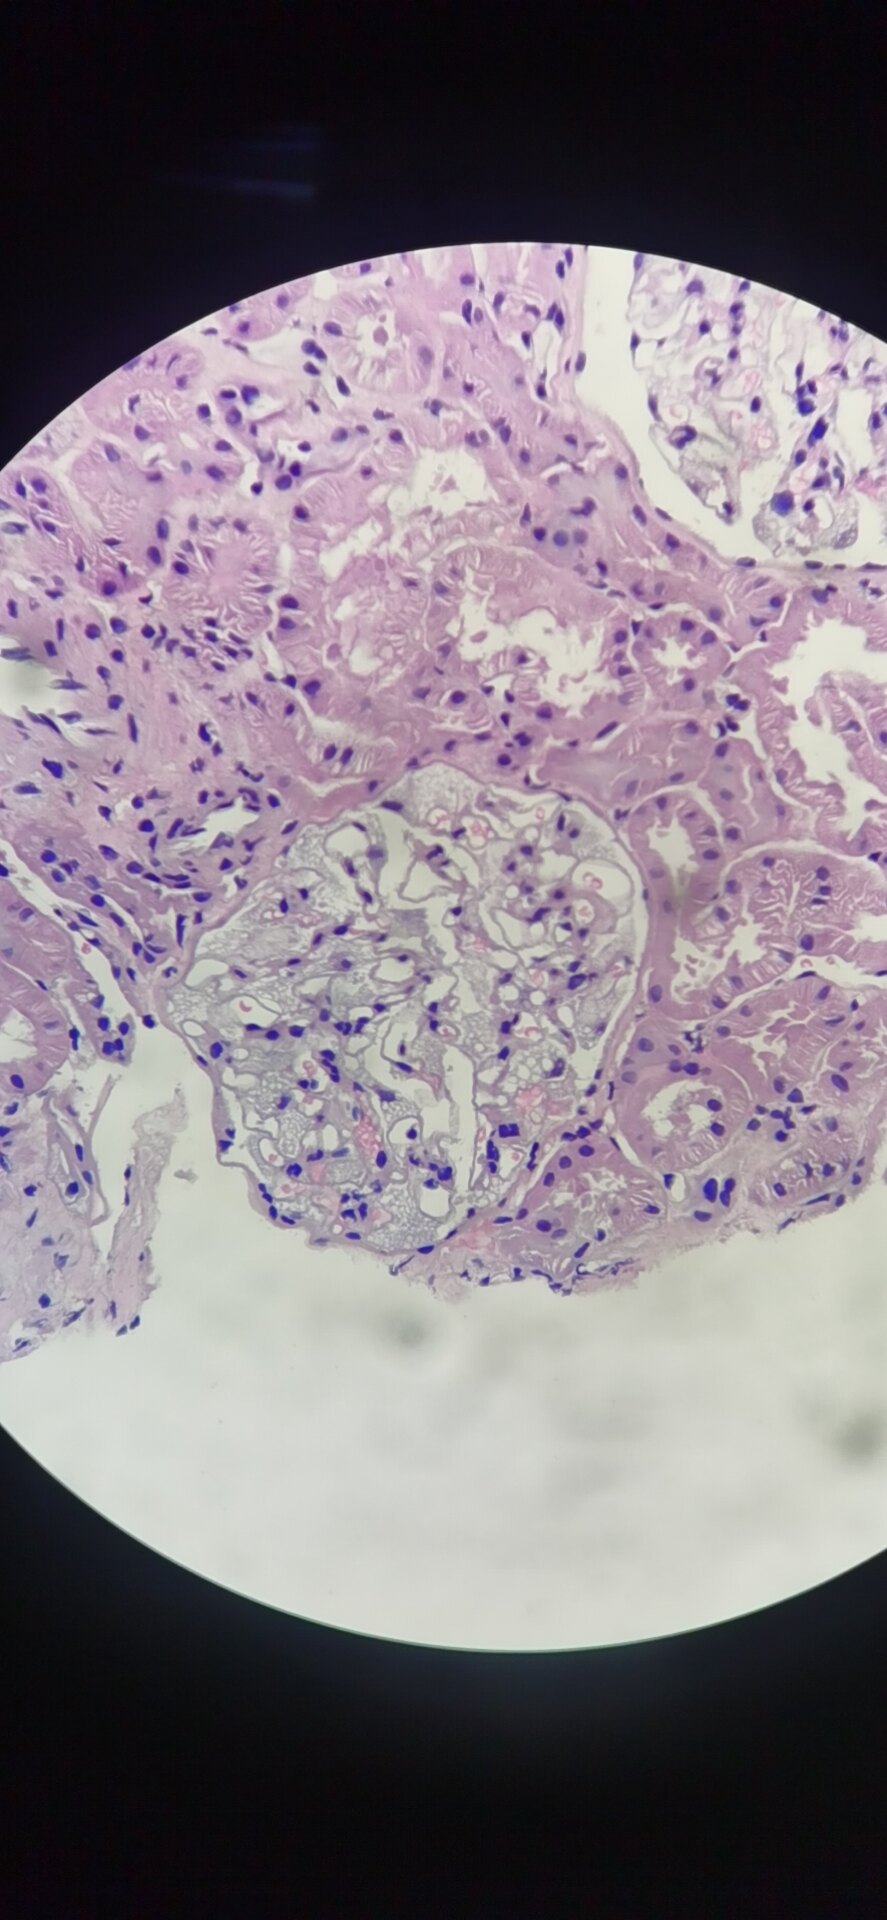

一例罕见的肾穿刺活检病例—怀疑法布里综合征fabrydisease - 好大夫